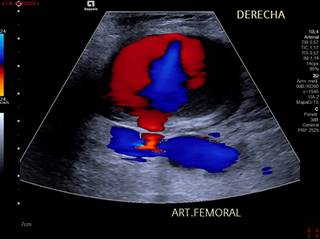

Hombre de 76 años con fibrilación auricular, a quien se le realiza coronariografía diagnóstica con abordaje femoral derecho. Después de ese evento en el postoperatorio se identifica evolución de lesión focal adyacente al sitio de punción, la cual era dolorosa e incrementaba su volumen e induración de forma diaria, por lo que se solicita ultrasonido Doppler de miembro inferior derecho para su valoración encontrándose pseudoaneurisma de la arteria femoral derecha (Figuras 1 y 2).

El diagnóstico de un pseudoaneurisma se debe realizar con ultrasonido Doppler, dentro del cual las características a buscar son la imagen en “Ying Yang”, velocidad picosistólica e índice de resistencia altos, tamaño, dependencia arterial específica y tamaño del cuello aneurismático. Se puede realizar tomografía o resonancia magnética complementaria en caso de requerirse para acompañar su valoración en términos de extensión en casos complejos.2